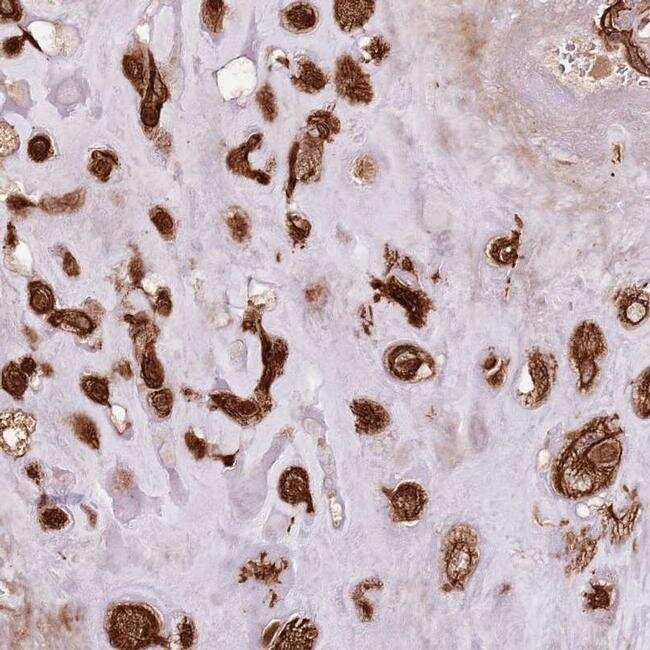

- Immunohistochemical analysis of FAM47B in human placenta using FAM47B Polyclonal Antibody (Product # PA5-61346) shows strong cytoplasmic positivity in decidual cells.